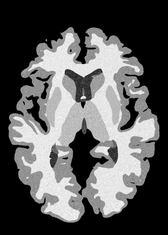

4.2 Registration to a 100 micron ex-vivo brain MRI volume

To showcase the efficacy of our method on real large scale images, we register a 250 in-vivo MRI image (Lüsebrink et al., 2017) to a 100 ex-vivo FLASH human brain volume (Edlow et al., 2019). This represents an inverse problem with more than 11.2B optimizable parameters (compared to 20M for clinical datasets), or 44.8GB of GPU memory. The entire problem does not fit on most GPUs, necessitating distributed multimodal registration. We optimize a composite transform - affine followed by a diffeomorphic mapping; details can be found in Section E.1. Multimodal deformable registration took 58 seconds on 8 NVIDIA A6000 GPUs, which is unprecedented at this resolution. Fig. 6 shows qualitative results, highlighting the ability to register highly detailed structures such as cerebellar white matter; these structures are not visible at macroscopic scales. The resultant advantages of performing registration at this scale can allow researchers to characterize the neuroanatomy at microscopic resolutions and allow morphometric analysis of cortical layers and subcortical nuclei among other structures.